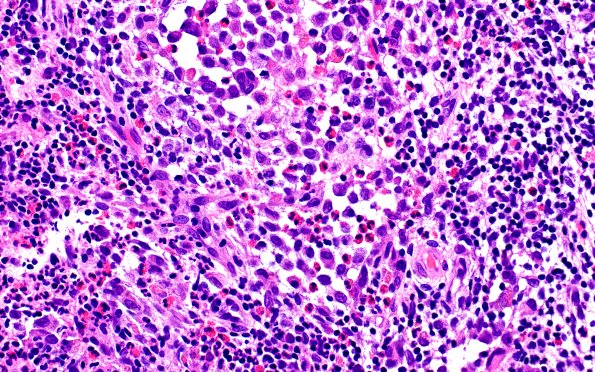

Washington University Experience | NEOPLASMS (HEMATOLYMPHOID) | Langerhans Cell Histiocytosis (LCH) | 24B7 LCH (Case 24) H&E 40X 5

The infiltrate includes scattered lymphoid aggregates, numerous eosinophils forming clusters and microabscesses, and aggregates of histiocytic cells with prominent nuclear grooves and nucleoli in a subset. (H&E)